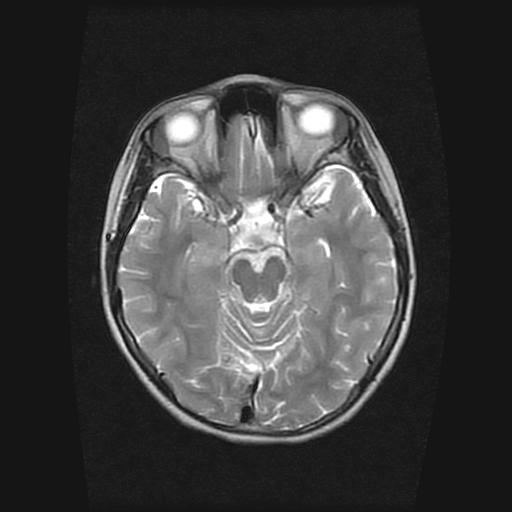

9岁女孩,三岁时诊断为癫痫,一直服丙戊酸钠,现患者一般情况良好,家长复查核磁片,看能否停药..

巨脑回

未见异常信号灶.

停药要结合临床,如无发作可以停。